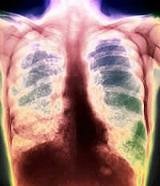

Эмфизема легких

Эмфизема – это процесс, при котором в легких происходит снижение подвижности тканей, повышается воздушность. Довольно часто поражаются все легкие, но иногда пораженные участки сочетаются и с участками нормальной ткани легких. Такая экзема называется буллезной.

Причинами возникновения заболевания является хронический запущенный бронхит, причинами образования буллем – наследственные факторы, тяжелые перенесенные болезни. Читать далее